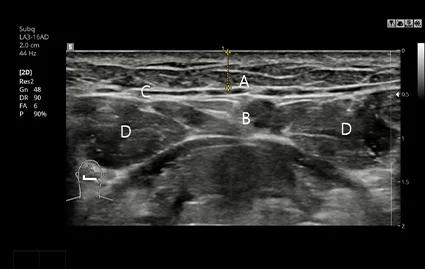

Preoperative CT and Ultrasound Imaging

CT scans and ultrasound examinations are performed prior to surgery to precisely analyze the location and size of the salivary glands. When necessary, a carefully planned, customized salivary gland reduction procedure is performed.